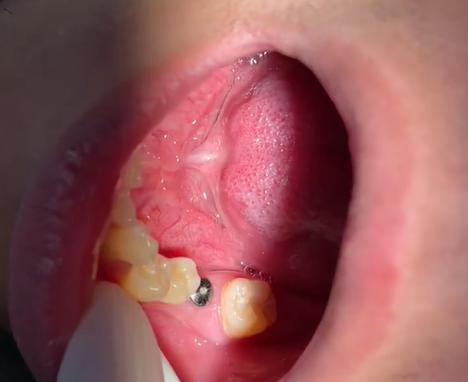

术后一周,我回到医院复查,医生检查后说“有点炎症,继续吃消炎药,再观察观察”,又过了两周,牙龈不仅没消肿,反而开始流脓,咬东西时种植体周围有明显的松动和异响,我急了,要求拍CT检查,结果出来后,医生的表情变得凝重:“种植体周围骨吸收严重,和牙槽骨没有长在一起,是‘骨结合失败’,必须马上取出。”

取出种植体的过程比第一次手术更痛苦,医生用器械敲击种植体时,我能清晰听到骨头碎裂的声音,术后伤口持续渗血,吃了半个月抗生素才勉强愈合,更糟的是,取出种植体后,我发现牙槽骨缺损了一块,医生说:“可能是感染导致的骨坏死,想再次种牙,得先做骨增量手术。”